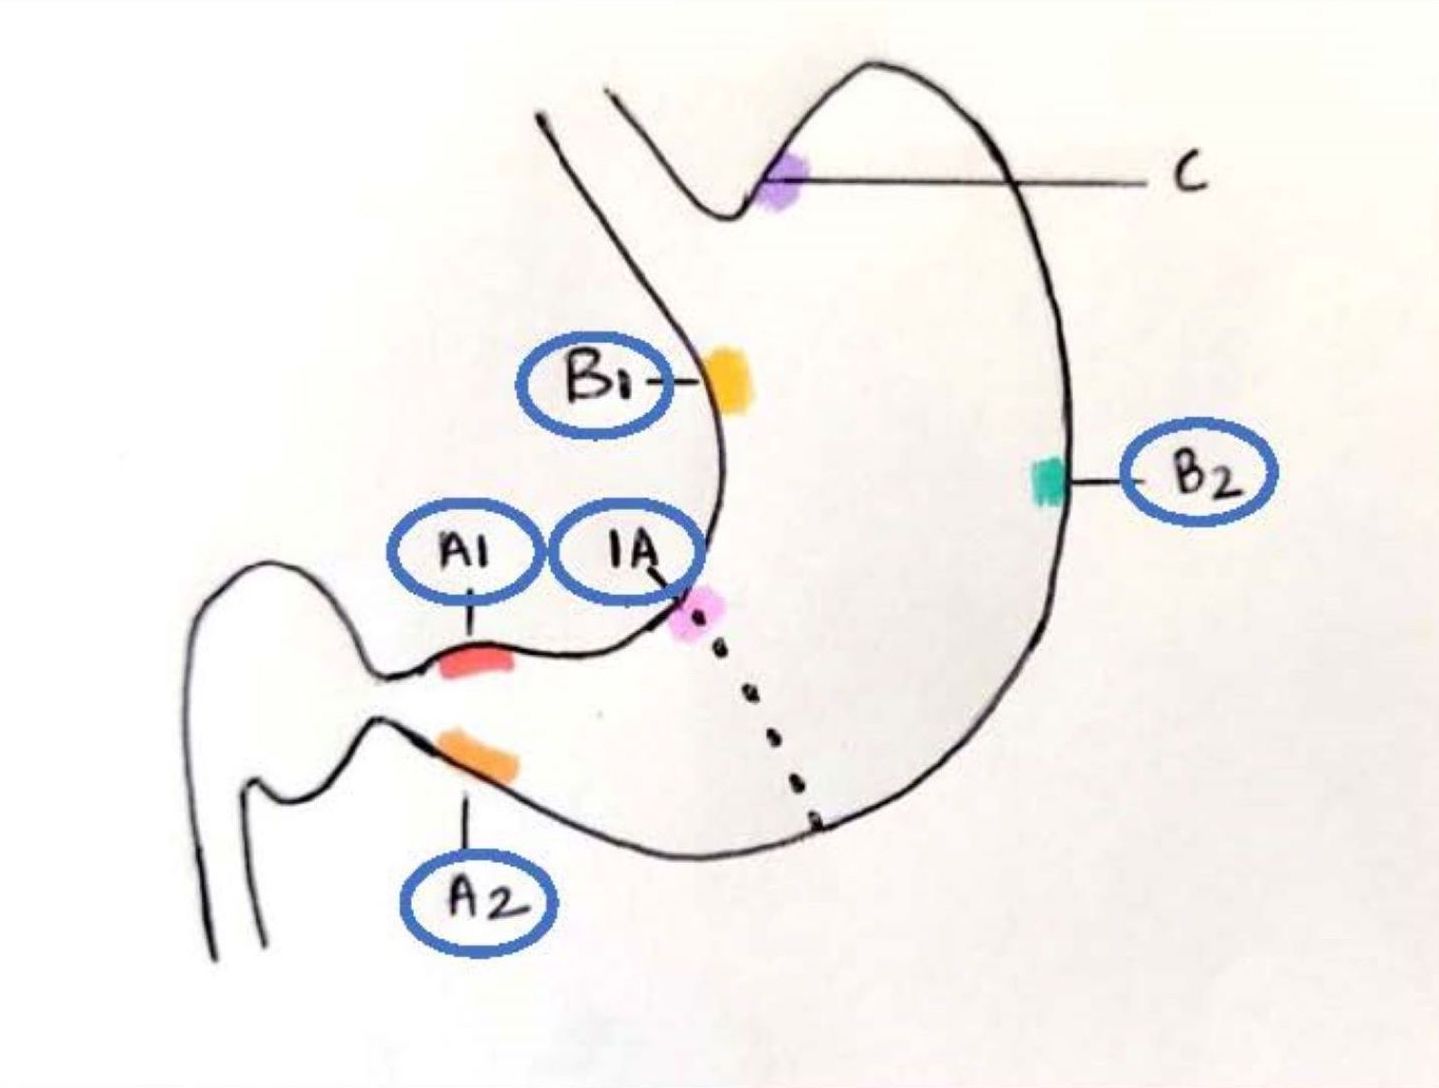

- All parts of the stomach can be affected; but it is most frequently observed in antrum and along the lesser curvature of stomach

- According to updated Sydney protocol, endoscopic targeted biopsies were recommended initially for grading and recently for staging of intestinal metaplasia

- It recommends at least 5 biopsies: 2 from antrum (1 each from lesser and greater curve, 3 cm proximal to the pylorus), 2 from body (lesser curve, 4 cm proximal to the incisura and midpoint of the greater curve) and 1 from the incisura (Am J Surg Pathol 1996;20:1161)

- Intestinal metaplasia is staged using the OLGA / OLGIM system; it is based on the grades of intestinal metaplasia in the antrum (including incisura) and body